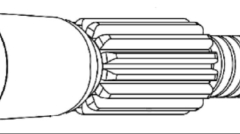

一种脊柱外科手术用锚定骨钉成果简介

发布:中医药创新转化研究院